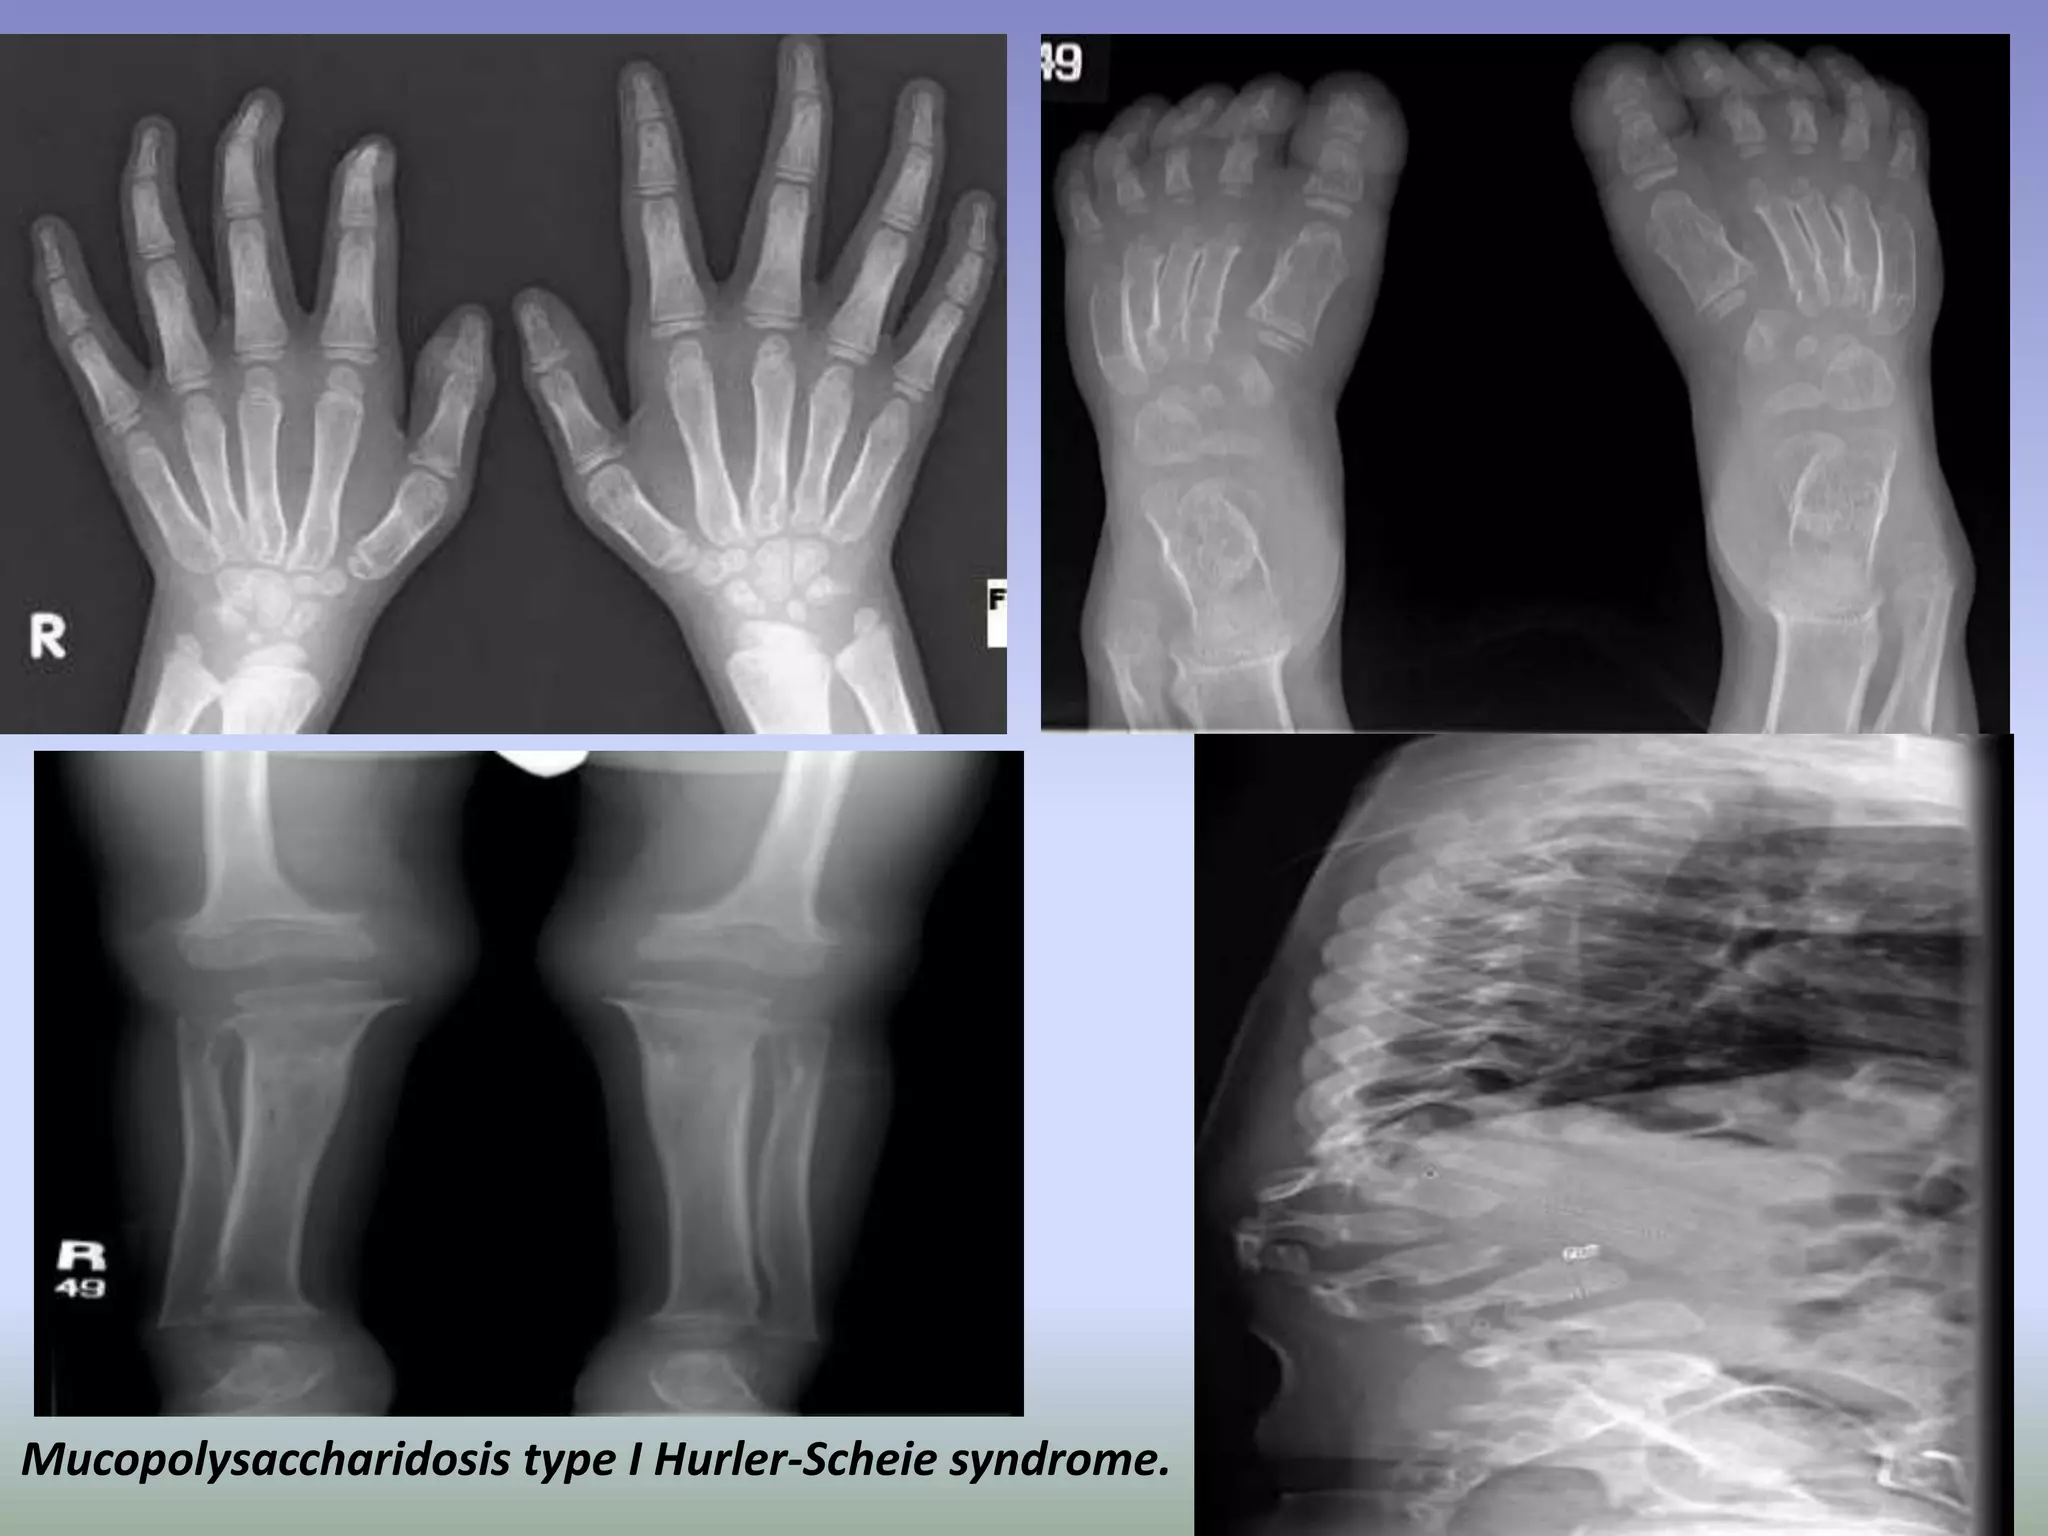

Mucopolysaccharidosis type I Hurler-Scheie syndrome.

Hurler Syndrome (MPS-IH).

(A) Lateral radiograph of

the skull shows a large “J”-

shaped sella and

underdeveloped mastoids.

Sinuses are hypoplastic. (B)

AP radiograph of the spine

and pelvis demonstrates

expanded anterior ribs,

hypoplastic ilia, and coxa

valga. (C) Lateral

radiograph of the spine

shows hypoplastic

vertebrae at the

thoracolumbar junction

with anterior beaking. (D)

Hand radiograph

demonstrates thick short

metacarpals and phalanges

with pointing of the

proximal metacarpals.